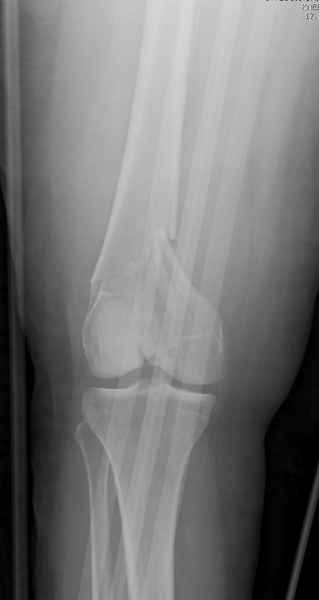

Имя     : distal femur.jpg

Тип     : image/jpeg

Размер  : 14488 байтов

Описание: отсутствует

Url     : http://weborto.net:8080/pipermail/ortho/attachments/20081001/5646c87e/attachment-0011.jpg